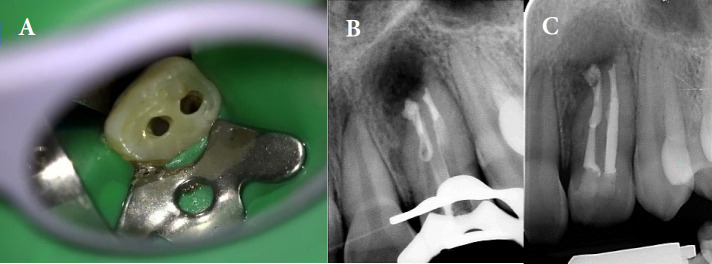

Dens invagination (DI) is a developmental dental anomaly characterized by the infolding of the enamel organ into the dental papilla. Type IIIb DI, involving deep invagination that extends apically along the root, poses significant challenges in endodontic treatment due to its complex anatomy. We describe a case of type IIIb DI in a 13-year-old female referred with the chief complaint of spontaneous pain on the left maxillary lateral incisor. Clinical examinations showed tenderness to percussion and palpation as well as a positive response to cold test with lingering pain. Cone-beam computed tomography (CBCT) confirmed the presence of type IIIb DI associated with a periapical lesion. The final diagnosis was irreversible pulpitis with apical periodontitis for main canal (distal) and pulpless and infected root canal system with secondary acute apical periodontitis according to Abbott classification for the other canal. Two separate access cavities were prepared with the guidance of CBCT. Root canal therapy was performed on both root canals, using photodynamic therapy (PDT) and ultrasonic-activated sodium hypochlorite for enhanced disinfection. Calcium-enriched mixture cement was used to obturate the apical third, followed by thermoplastic gutta-percha in the middle and coronal thirds. The patient was asymptomatic at 6- and 12-month follow-ups, with radiographic evidence of complete healing. This case highlights the effectiveness of conservative endodontic treatment using PTD in managing complex DI cases, with a focus on maintaining tooth structure and achieving long-term success.

Abstract Image